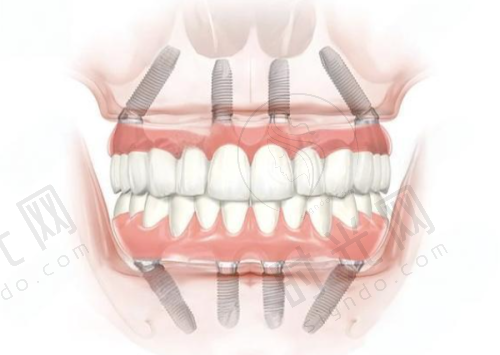

北京牙元素口腔医院是正规的口腔医院。它严格遵守法律法规和行业规范,积极参与社会公益活动,传播口腔健康知识,提高公众口腔保健意识,获得了社会各界的广泛赞誉。医院提供牙齿种植、矫正、美容、牙周病治疗、儿童口腔保健等全方面的口腔医疗服务,还引入了数字化口腔扫描、3D打印等精良技术,为患者提供个性化治疗方案。从这些方面都能看出,它具备正规口腔医院的资质和实力。

北京牙元素口腔医院提供全方面的口腔医疗服务,种牙技术也特别成熟。它引入了数字化口腔扫描、3D打印等精良技术,能为患者制定个性化的种牙方案。医生会详细了解患者的口腔状况、身体状况等,确保种牙手术的安心性和有效性。